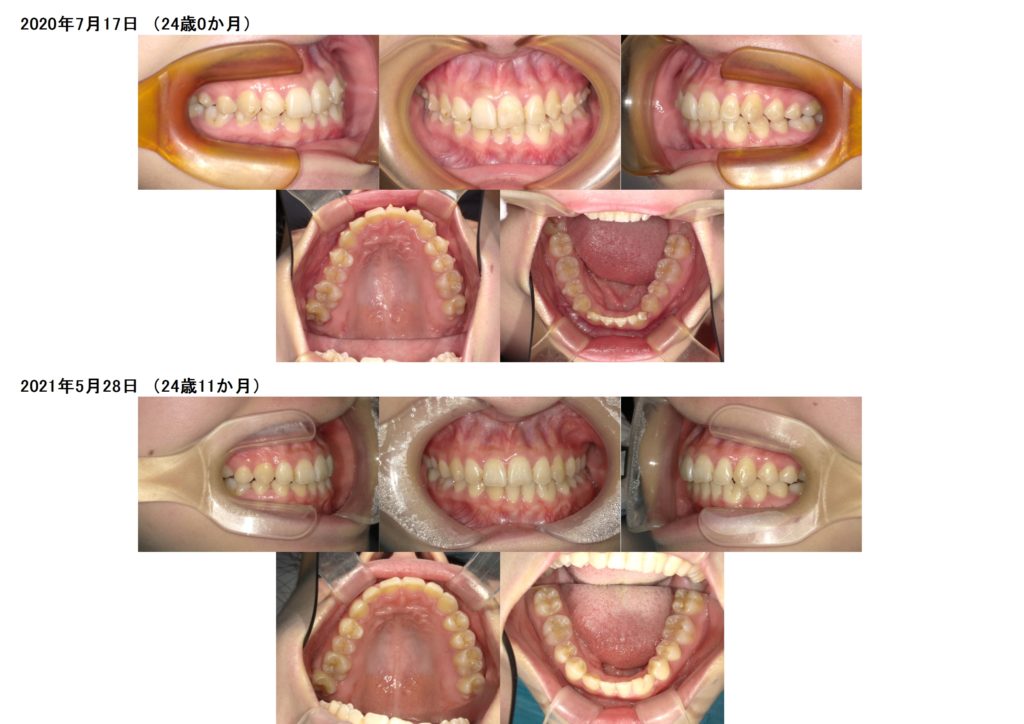

随分と形が変わったのがわかりますよね☆

↑上の写真にアタッチメントが着いているのが分かりますよね。

マウスピースを使用して治療が完了しました。

今はしっかりと歯並び、噛み合わせを定着させるために保定期間中になります。